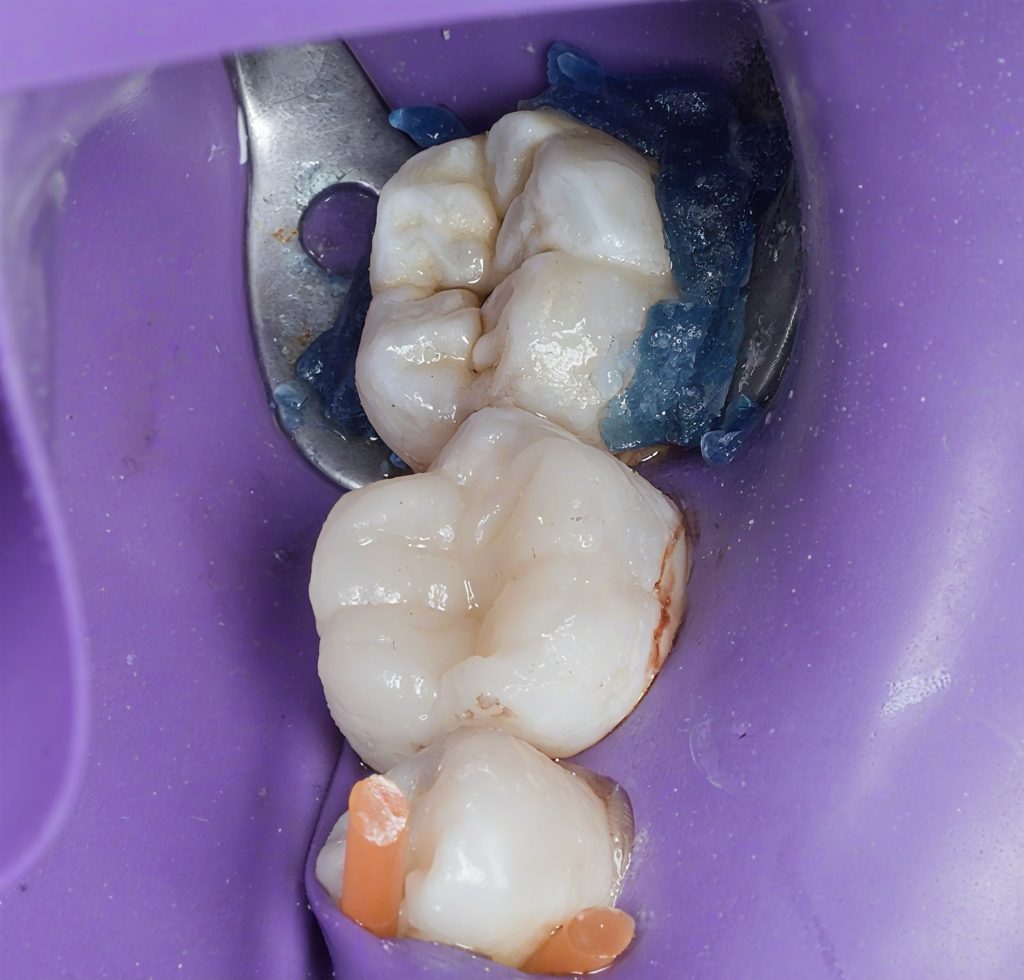

Isolation

Absolute rubber dam isolation was established prior to access preparation. Isolation was maintained throughout both endodontic and restorative phases to ensure a contamination-free environment and optimal bonding conditions.

Core Build-Up

A bonded core build-up was performed under rubber dam isolation. The goal was to:

- Seal the access cavity

- Reinforce weakened walls

- Provide a stable foundation for cuspal coverage

Cuspal Coverage Restoration

Given the extent of tooth structure loss and the functional demands on mandibular first molars, cuspal coverage was indicated. Occlusal anatomy was rebuilt using a biomimetic approach to restore:

- Functional cusp inclines

- Proper occlusal contacts

- Even stress distribution during mastication

Finishing and polishing were completed to achieve smooth margins and harmonious occlusion.